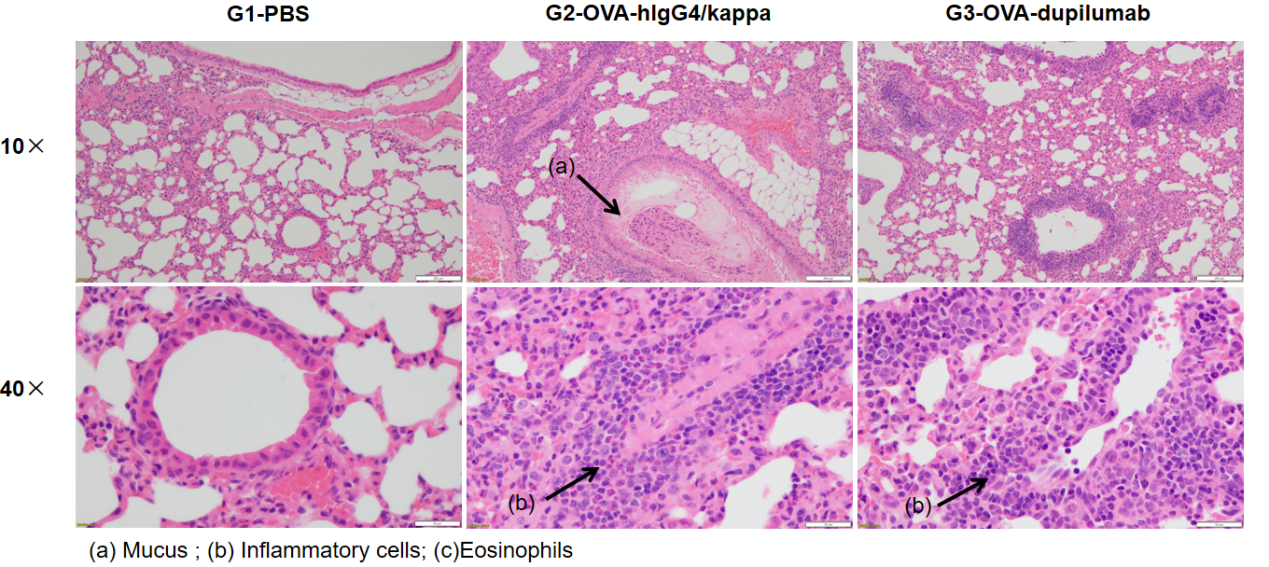

H&E staining of lung tissue in OVA-induced B-hIL4/hIL4RA asthmatic mouse model. Histopathological analysis showed no airway inflammation in G1 controls. G2 (OVA-only) mice exhibited marked vascular and peribronchial inflammation (b) and increased mucus secretion (a), confirming successful asthma model induction. Dupilumab-treated mice (G3) showed reduced inflammatory infiltration and mucus production. These findings support the use of OVA-induced B-hIL4/hIL4RA mice for evaluating anti-asthma therapeutics.